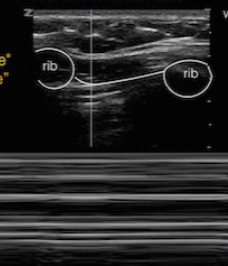

A

pneumothorax (bar code sign)